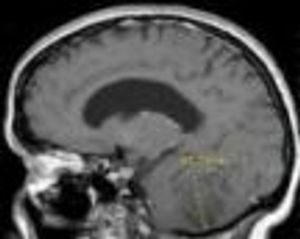

Lhermitte-Duclos disease is a rare, slow-growing, benign lesion of the cerebellum and is considered a hamartomatous tumor of the cerebellar cortex.